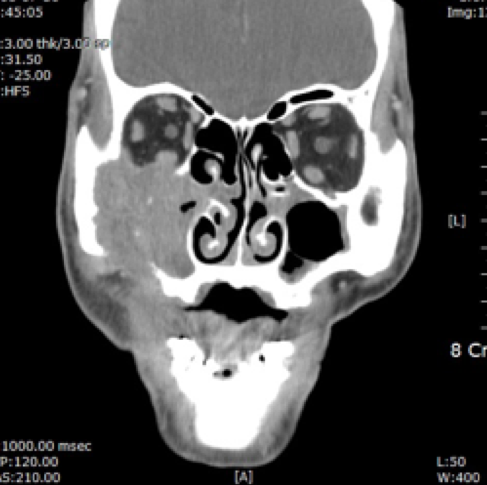

- 전산화 단층촬영 (CT 촬영)

전산화단층촬영 |

전산화단층촬영